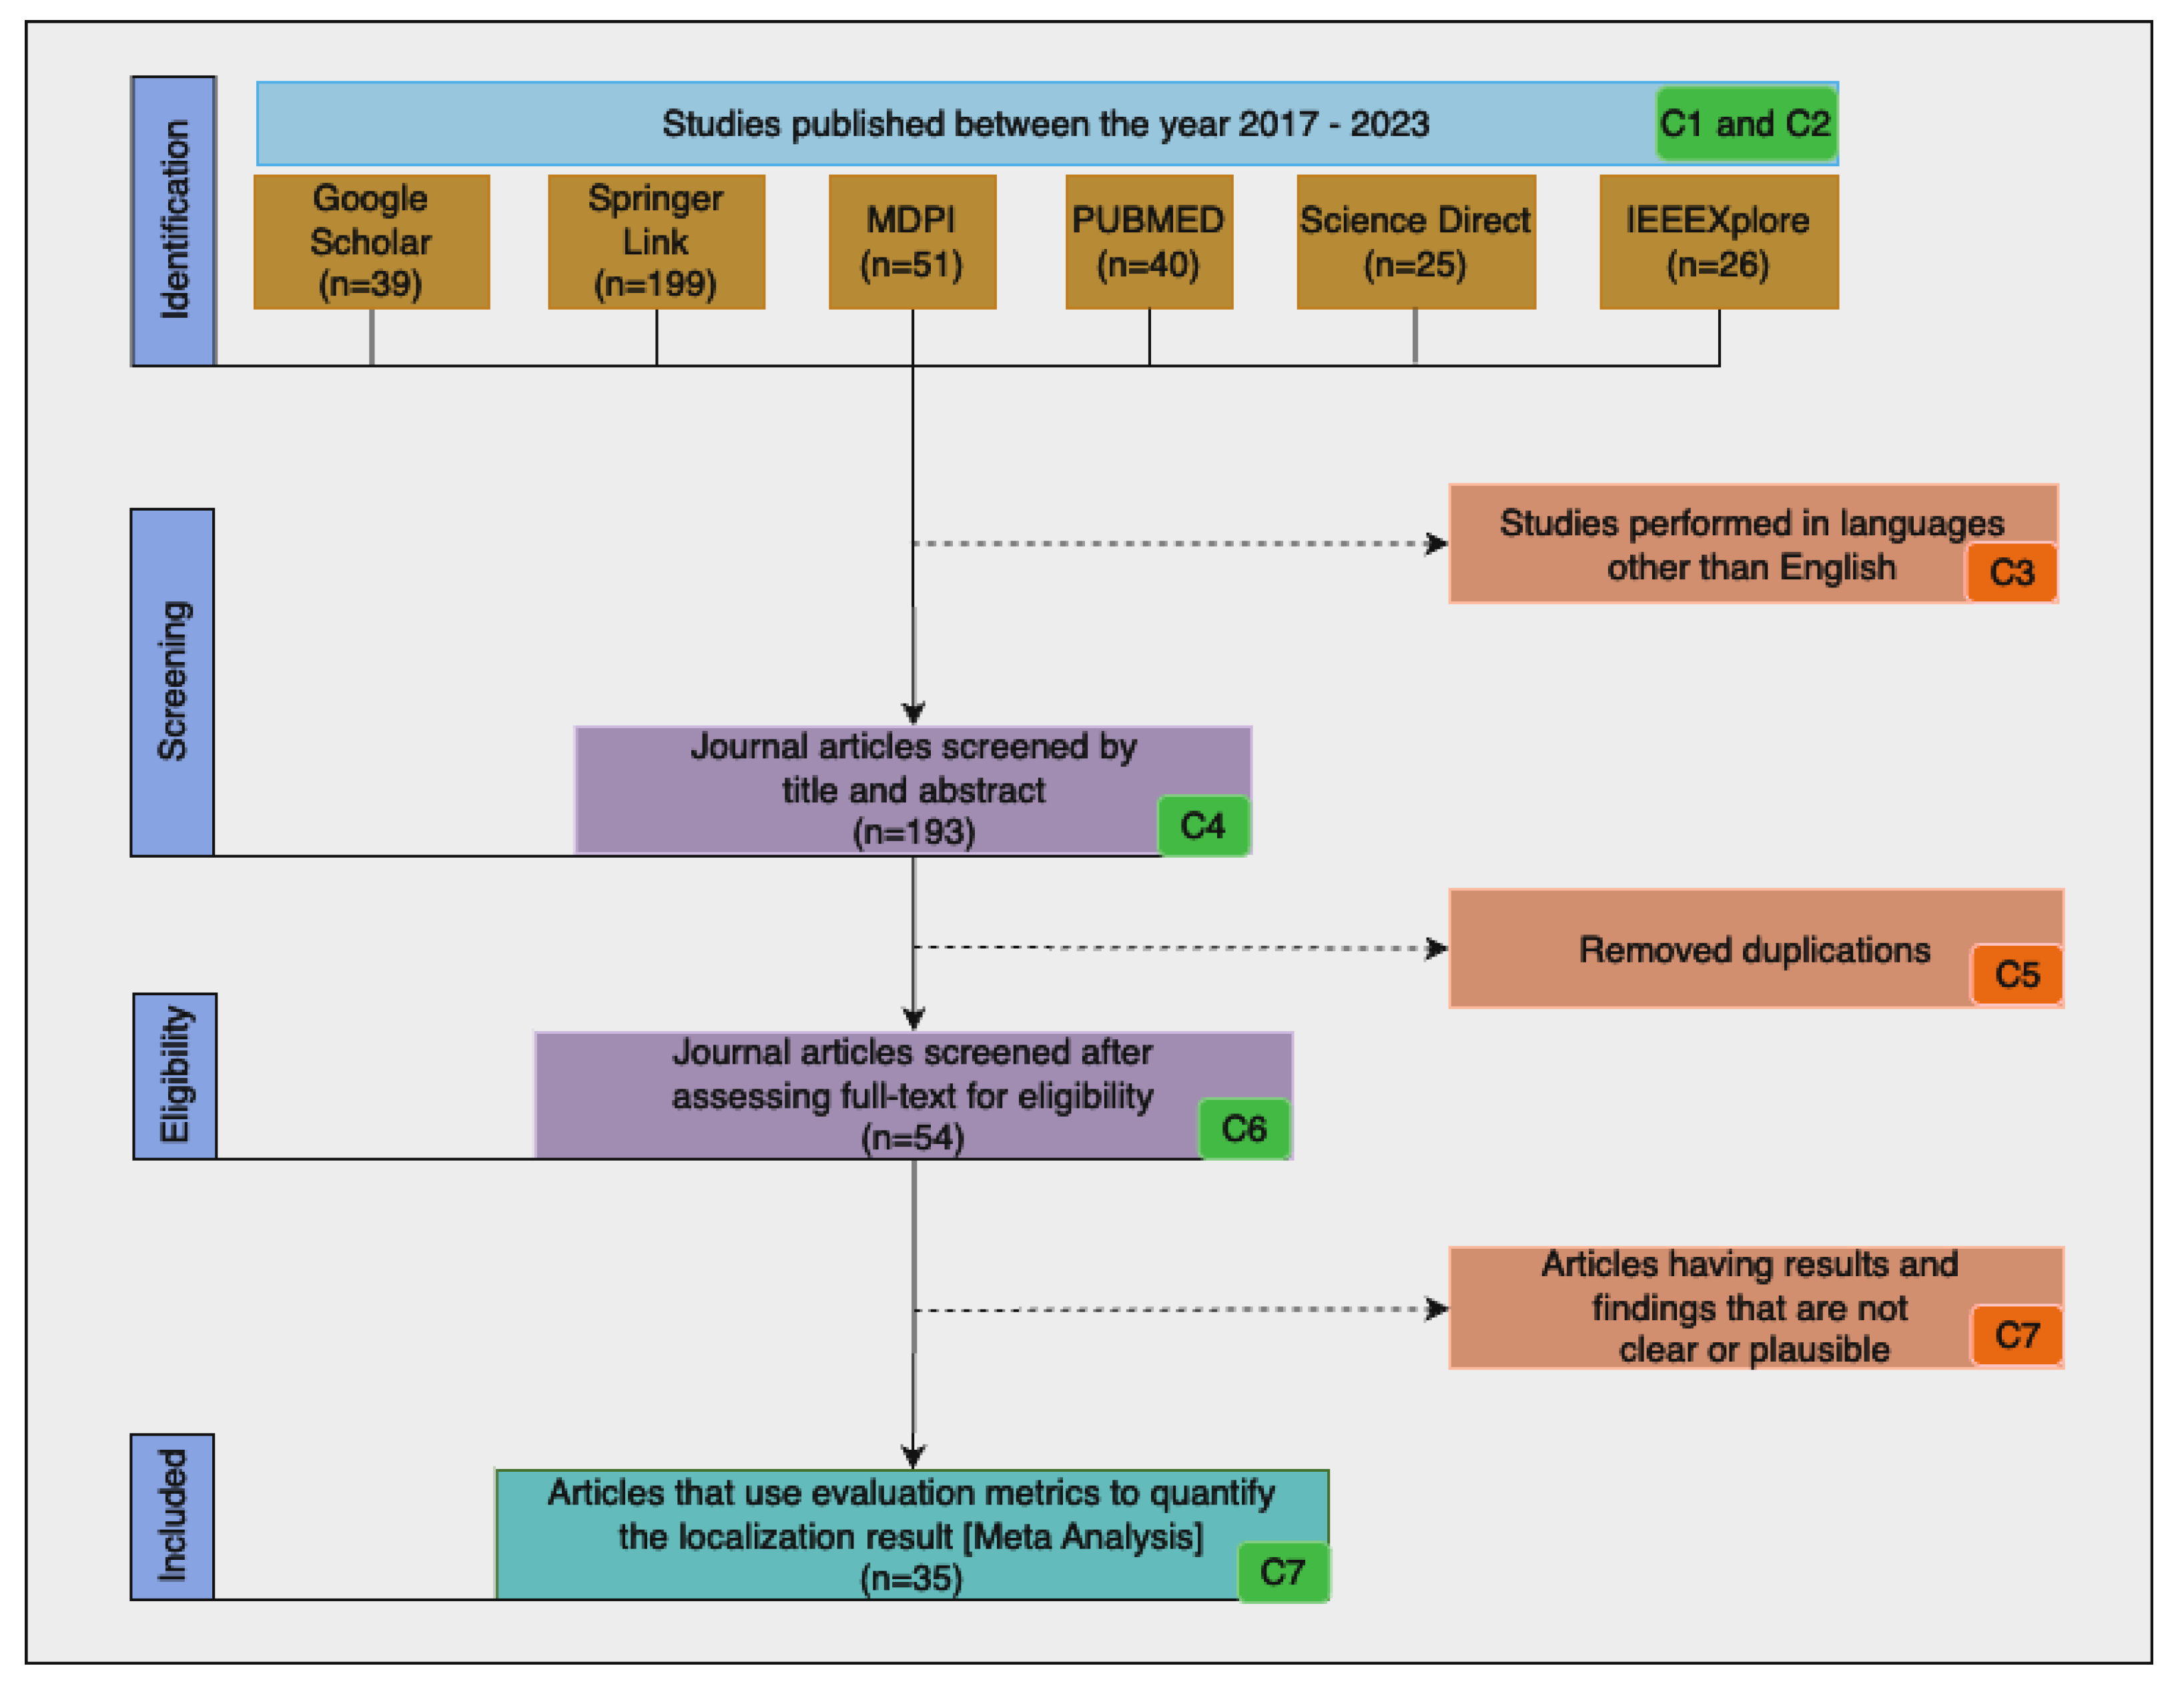

3. Methodology

| Algorithm 1: The steps followed to complete the review as per the PRISMA guideline. |

| ID | Inclusion | Exclusion | Description |

|---|---|---|---|

| C1 | X | - | Studies performed between the years 2017 and 2023 |

| C2 | X | - | Studies that are original article and conference papers |

| C3 | - | X | Studies performed in languages other than English |

| C4 | X | - | Studies that involve the localization and segmentation of pulmonary TB in a chest X-ray |

| C5 | - | X | Duplicate publications |

| C6 | - | X | Studies that use machine learning or DL methods |

| C7 | - | X | Studies that are not presented with clear and plausible results |

| C8 | X | - | Articles that use evaluation metrics to quantify the localization result |